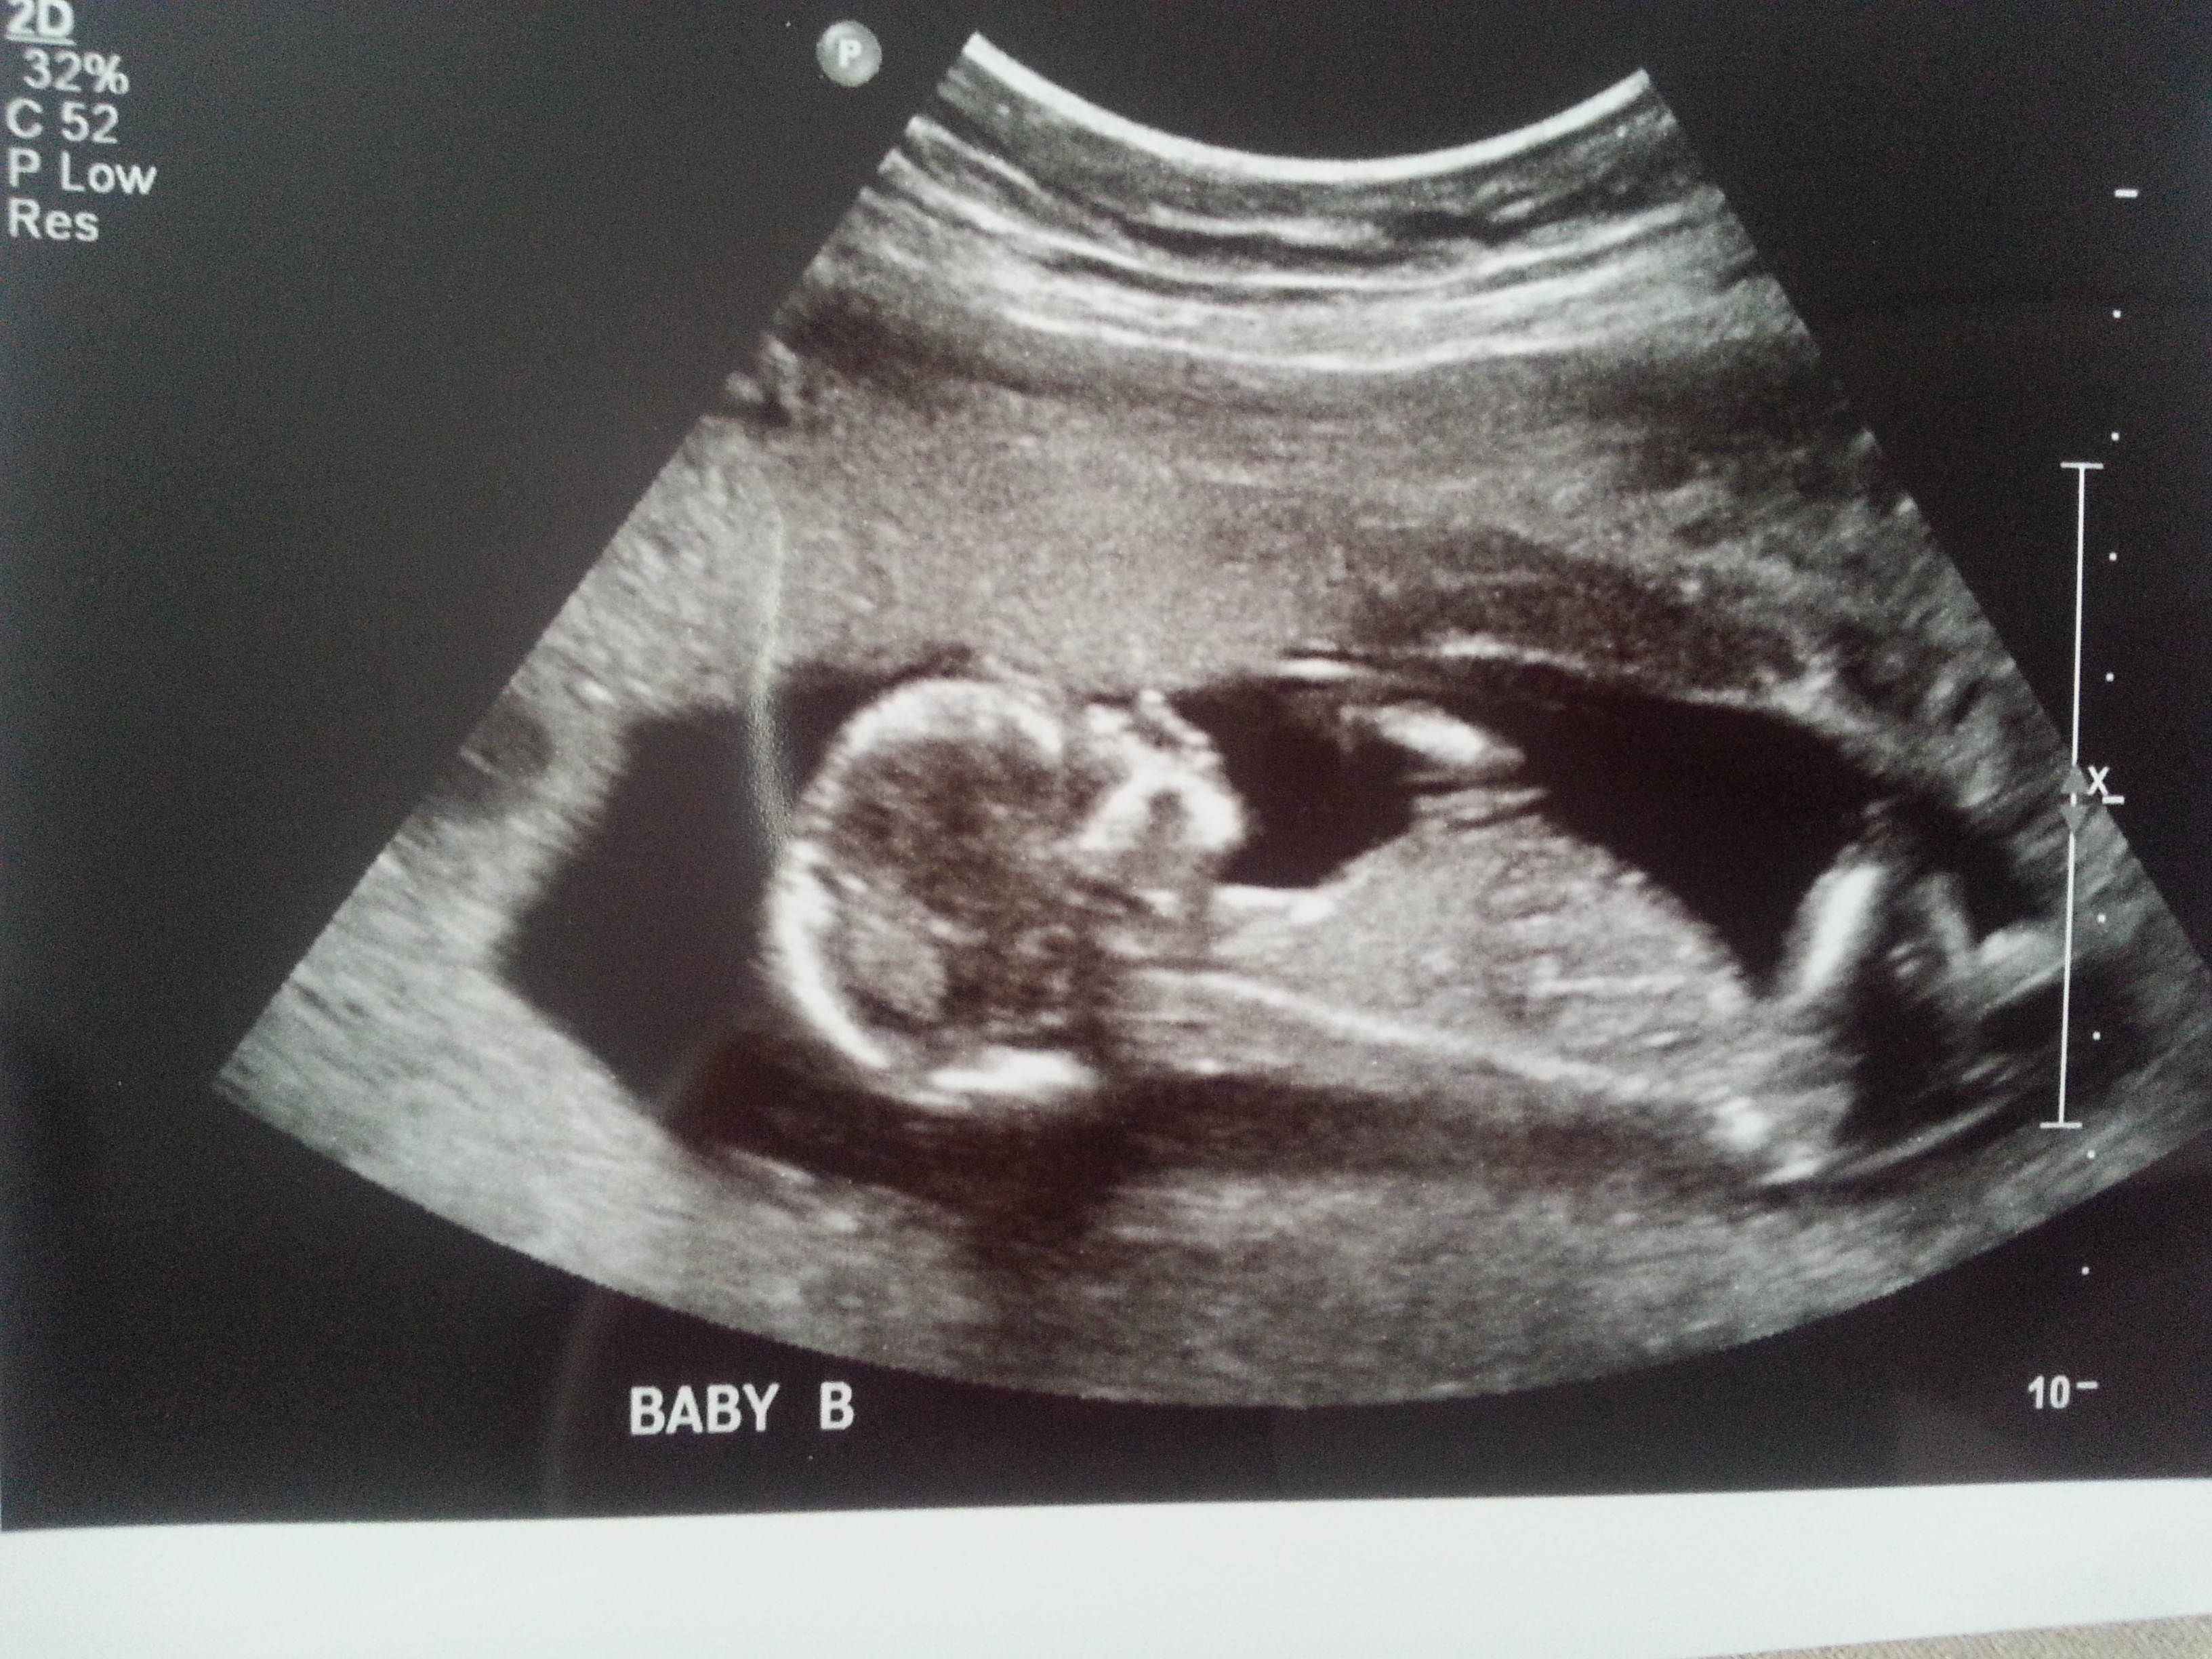

I was 12weeks 6 days and measuring 13weeks 3 days.

Maybe boy/girl. Not the best shots though!

I think I'm seeing a very boyish nub for baby B. Baby A not as sure. I hope that's your girl! Congrats and good luck!

On your second pic of baby B I'm looking at the little line between the legs that's almost sticking straight up.... very boyish "angle of the dangle".